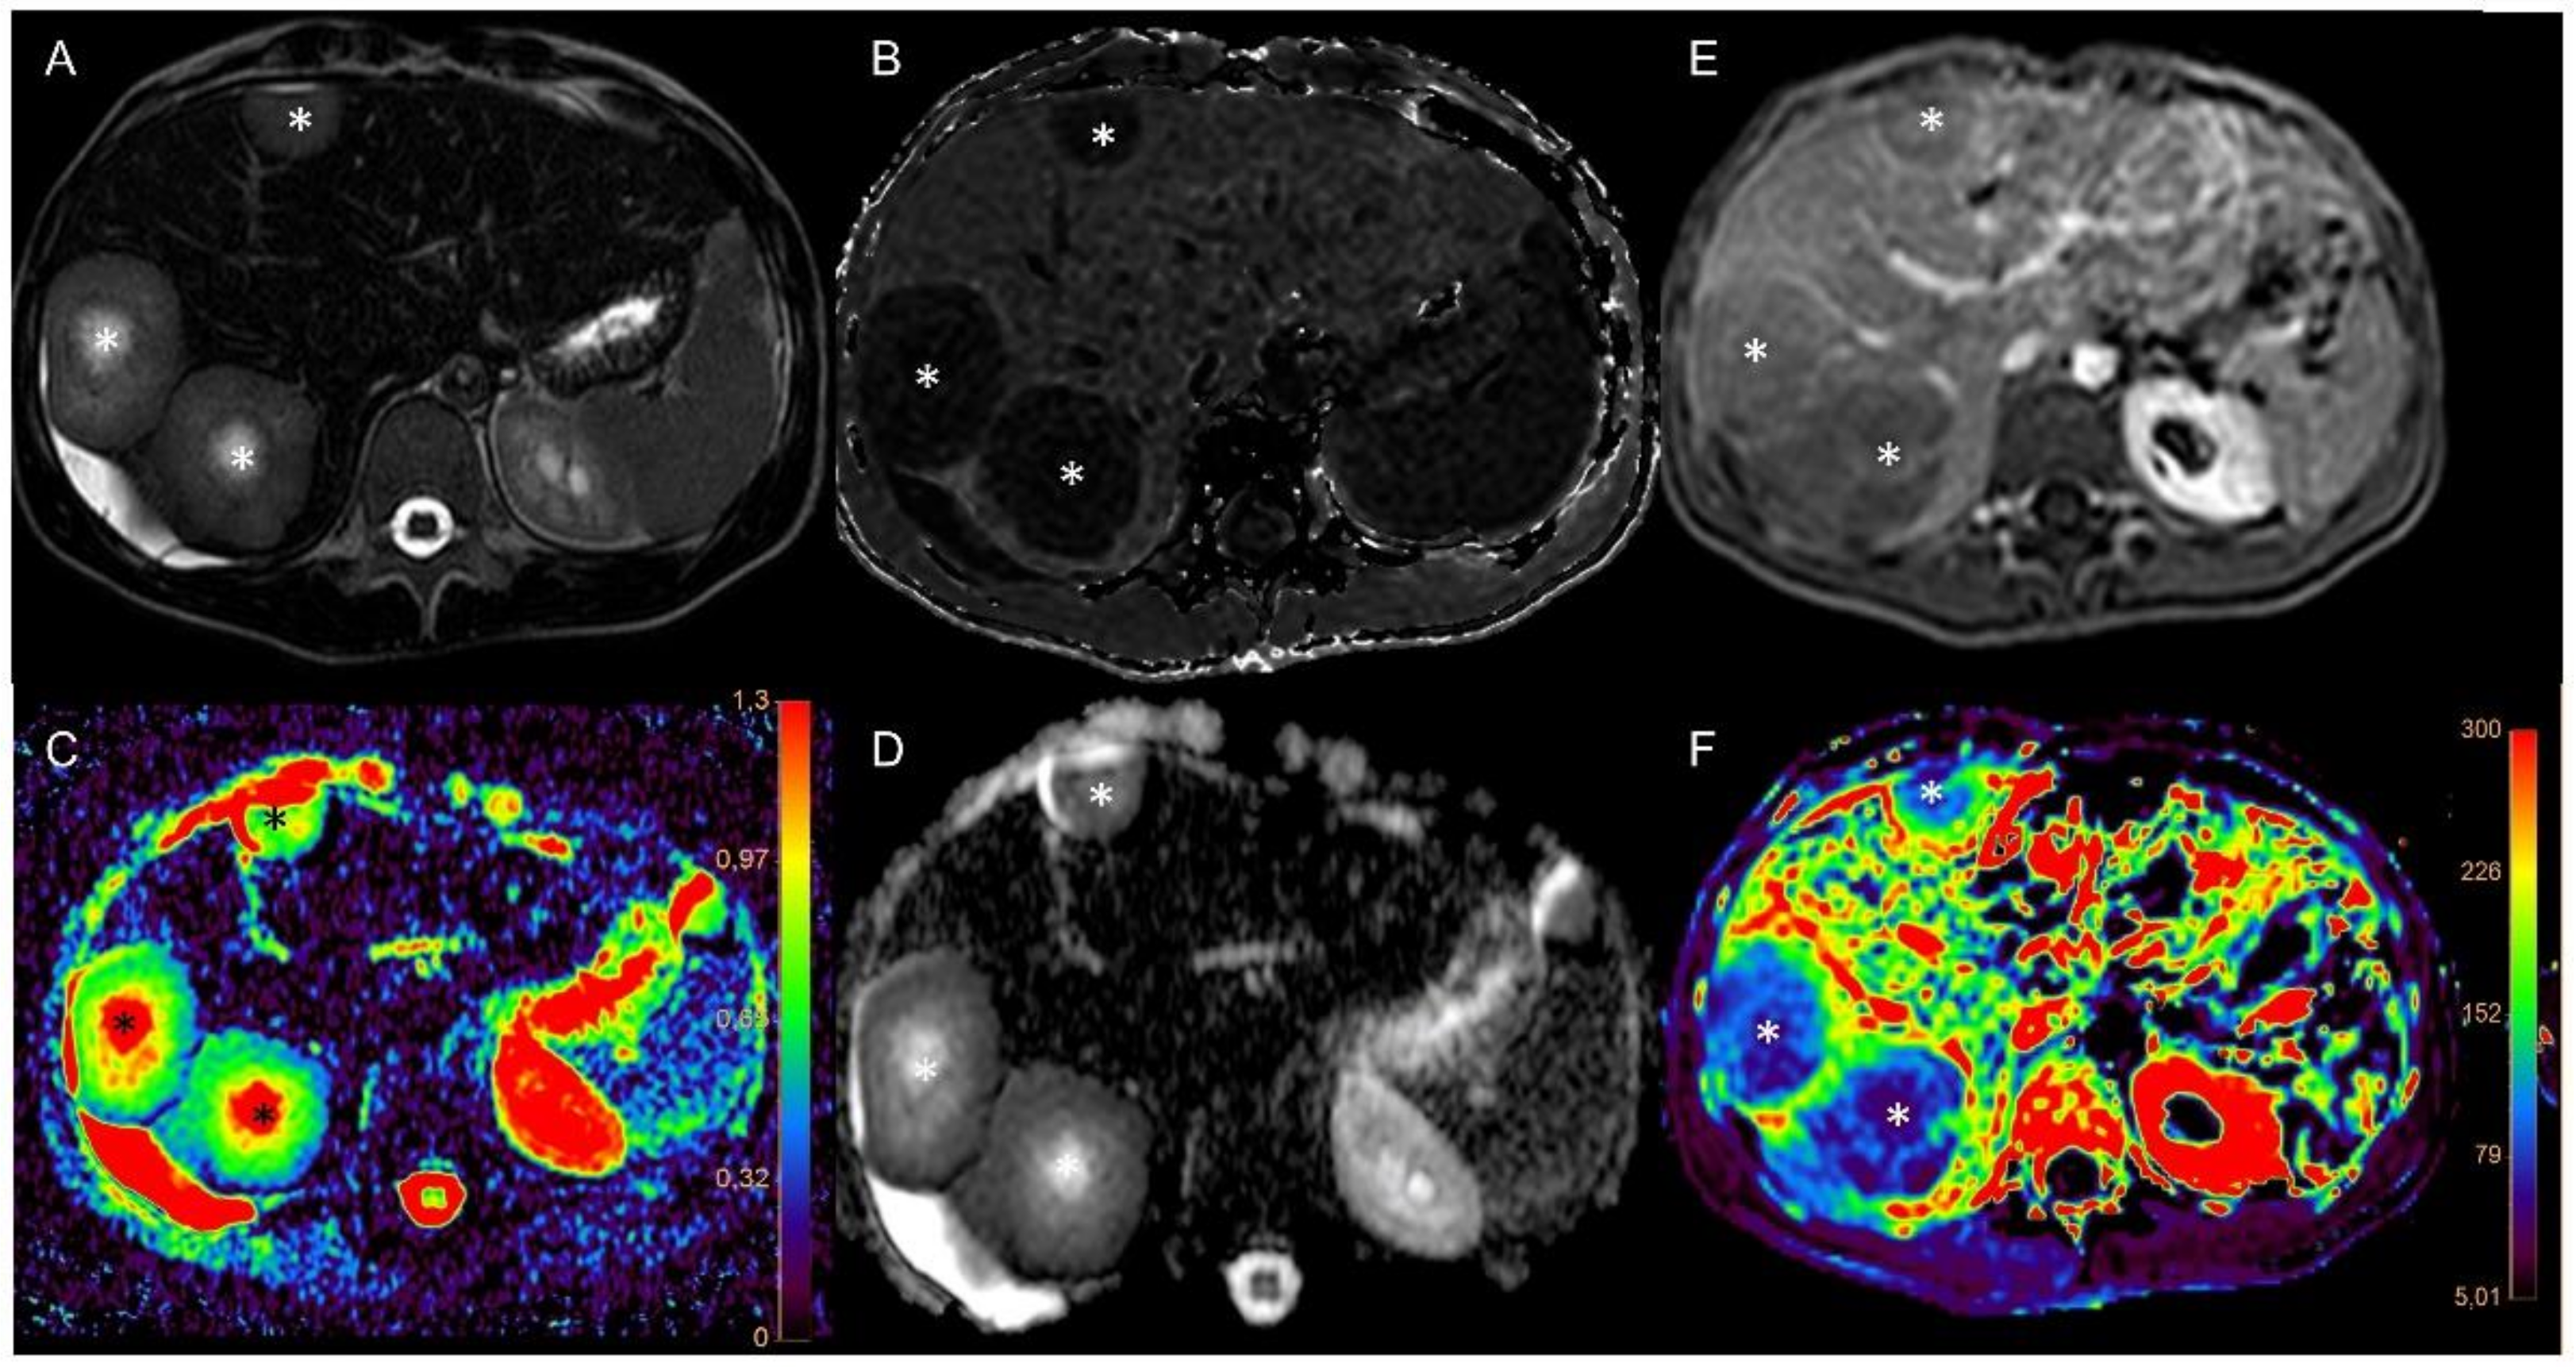

3.1. Imaging of Target Hit and Effectiveness

3.2. Correlation Analysis